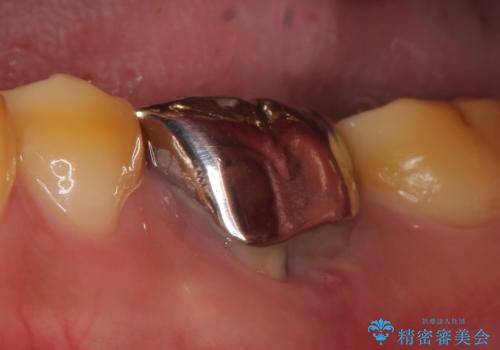

オールセラミッククラウン 他院にて抜歯と言われた歯の治療